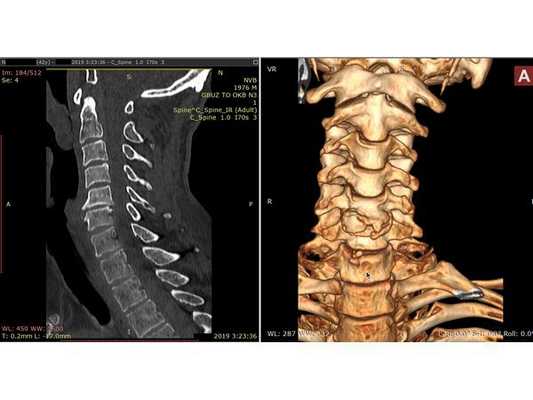

По результатам КТ шейного отдела позвоночника травматической патологии не выявлено, отмечается сглаженность шейного лордоза, спондилёз (естественное изнашивание и старение позвонков с формированием нежелательных костных разрастаний), наиболее выраженный в позвонках C5-C6. МРТ исследование по техническим причинам выполнено на следующий день: выявлен стеноз (сужение) позвоночного канала с уровня C3-C4 до уровня C5-С6 с формированием очагов миелопатии (поражения спинного мозга) с уровня C3 до C6; отмечается "свечение" тела С5 позвонка, свидетельствующее о наличии гемокомпонента в ячейках губчатой костной ткани. Предположительно, гемокомпонент появился вследствие компрессии тела С5 позвонка в момент травмы.

МРТ шейного отдела позвоночника: в Т2-режиме видны миелопатические очаги в сегменте С3-С6 на фоне абсолютного стеноза с уровня С3-С4 до С5-С6